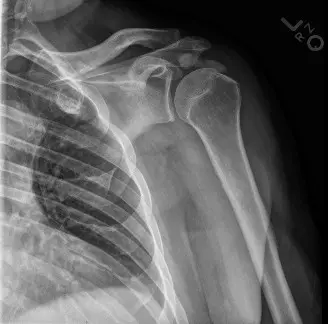

الشكل 1: صورة أشعة سينية بسيطة توضح ترسبات تكلسية بجوار النتوء المرفقي، متوافقة مع تكلس وتر العضلة ثلاثية الرؤوس في المرفق.